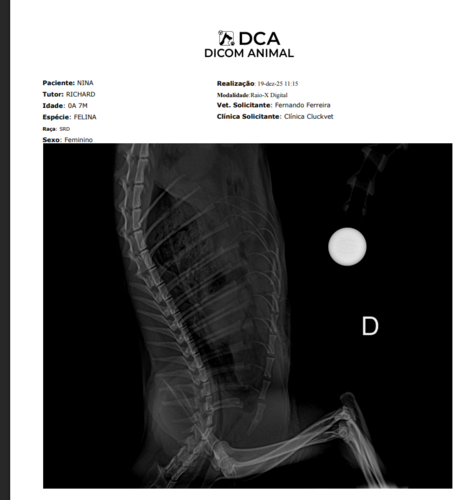

Meu nome é Richard, e Minha gatinha nina foi atropelada…, ela quebrou a perninha e rompeu o Diafragma dela, tive que fazer uma cirurgia de emergencia pois os orgãos dela tinham subido para o torax e estavam comprimindo o coração e pulmão dela, ela quase morreu. O preço da cirurgia foi de R$ 2300,00, e ainda falta a cirurgia da perninha dela que ainda segue quebrada. Todos esses custos são demais para mim bancar, e eu preciso de ajdua para fazer isso… A cirurgia de emergencia foi só para ajeitar o torax dela que estava bem delicado. Mas ainda preciso pagar e planejar a outra cirurgia dela, para a perninha dela, que ainda nem sei quanto vai custar…. Quem puder e quiser ajudar, por favor considere uma doação, qualquer quantia vai me ajudar e muito. Deixarei as imagens do raio X abaixo. E tentarei manter tudo atualizado para acompanharem o progresso.